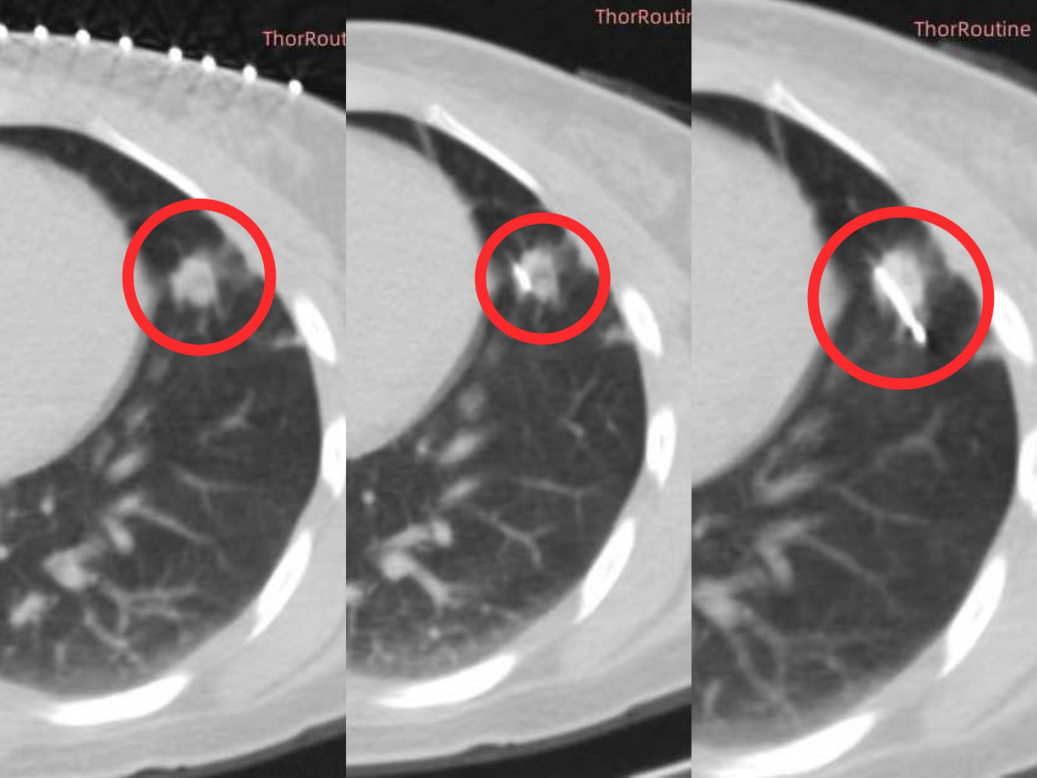

手术当天,在 CT 的精准引导下,只见细针缓缓穿过皮肤、肺组织,稳稳「扎」进左肺病灶 ,几乎没有出血。

随后,氩气快速输送,病灶温度骤降至 -140℃,CT 影像上清晰地看到病灶变成了 「白色冰球」;6 分钟后切换氦气升温,冷热交替间,肿瘤细胞逐渐失去活性。术中,医师全程监测王阿姨的心率、血压等生命体征,确保不出现意外。

1 小时后,手术顺利结束!复查 CT 显示:病灶完全被 「冻灭活」,术后复查肺部 CT 心脏、血管没有任何损伤,也没有出现气胸、咯血等并发症。观察 2 天后,王阿姨顺利出院,回家继续后续康复。